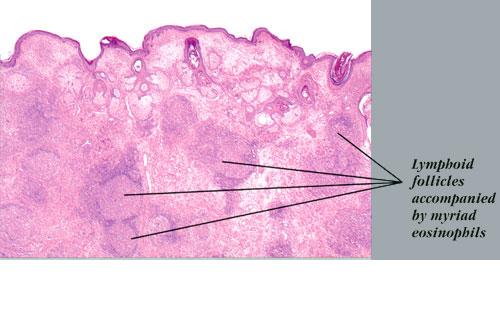

Histopathologically, the dermis and/or subcutis exhibit hyperplasia of small blood vessels lined by plump endothelial cells similar to those present in the high endothelial venules of lymphoid tissues. These venules are a major point of lymphocyte trafficking between the blood and the paracortical T-cell domain of lymph nodes. Surrounding these hyperplastic vessels is a dense infiltrate composed of small lymphocytes, plasma cells, histiocytes, and eosinophils. The latter are typically prominent but may be absent in some cases. There are usually multiple secondary lymphoid follicles with prominent germinal centers, particularly in the subcutaneous lesions. In general, lesions are more superficial and the vascular features are more prominent in AHLE, whereas lesions are deeper and the lymphoid features are more prominent in Kimura disease.